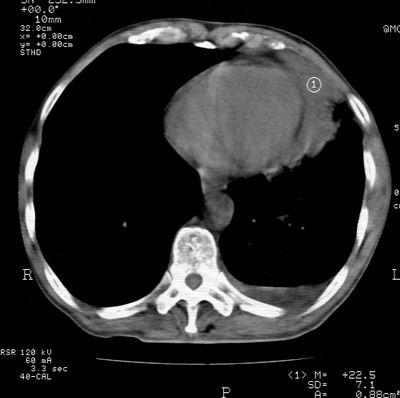

标题: CT24000:M65,胸痛,胸闷月余,既往慢支,肺气肿,肺心病 [打印本页]

标题: CT24000:M65,胸痛,胸闷月余,既往慢支,肺气肿,肺心病

左肺门肿块,相应支气管闭塞,左肺上叶、舌叶大片及散在高密度影,部分呈不张改变,两肺纹粗乱,左侧胸腔积液。考虑左侧中央型肺癌伴阻塞性改变。

左肺门见巨大软组织肿块影,直径约--,境界清,左上肺叶支气管变窄,左上肺舌叶见大片状密实影,余肺纹理增多、紊乱、纤细、部分网格状,两肺透亮度增高,纵隔内见增大多发淋巴结影,心影略左偏,左侧少量胸腔积液。

左侧中央型肺癌伴左上肺舌叶不张、纵隔淋巴结转移,左侧少量胸腔积液。